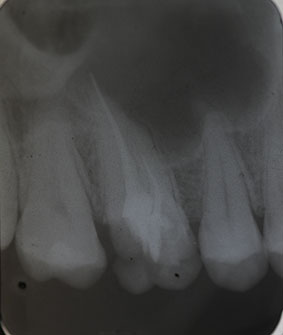

Nach Darstellung aller Wurzelkanaleingänge wird in einem zweiten Schritt das frakturierte Wurzelkanalinstrument dargestellt (Abb. 3 u. 4). Hierfür verwenden wir den Aufsatz 3E des Tigon+. Durch die schmale und lange Form des Instruments erreichen wir einen tiefen und schmalen Zugang.

Abb. 3 u. 4: Zustand nach Revision des Wurzelkanals und Darstellung des frakturierten Instruments.

Sofern es sich um ein kleines Frakturstück handelt, kann es durch aktive Übertragung von Energie des Ultraschalls zu einer Lockerung des Fragments kommen. Lockert es sich nicht, so „umkreist“ man das Instrument vorsichtig, um es anschließend mit einer Spritze gefüllt mit Palavit G zu greifen, zu fixieren und zu entfernen (Abb. 5). Nach Entfernung des Instruments erfolgt eine Kontrollaufnahme (Abb. 6).